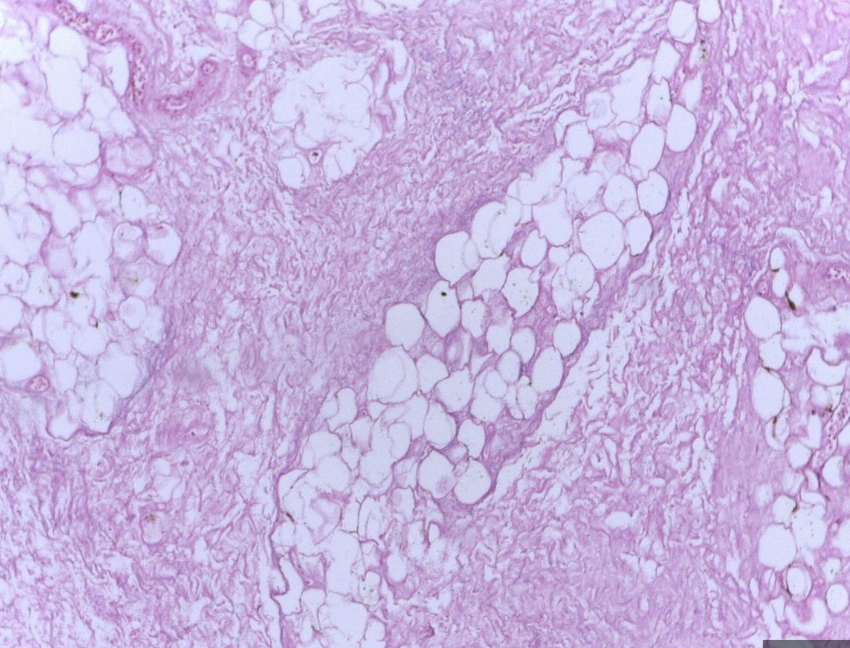

What is Fat necrosis of the breast?

What is its typical clinical presentation?

Inflammatory reaction to damaged adipose tissue

Typical presentation in

• obese, middle aged women presenting with

• painless breas mass, mammographic lesion

• (can mimic carcinoma with skin tethering, nipple retraction)

Causes – trauma, radiotherapy, surgery, nodular panniculitis

What are histological findings of fat necrosis on cytology?

Cytology – empty fat spaces , histiocytes and giant cells